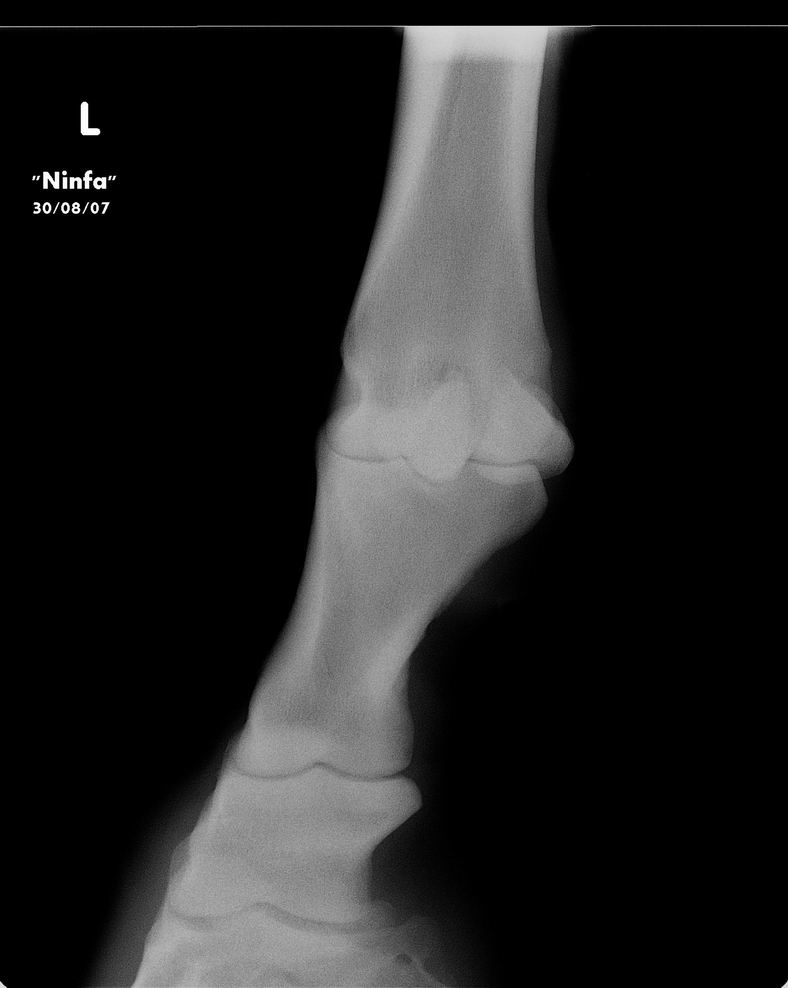

Posted on Monday, Nov 16, 2009 - 4:55 pm: Dear Dr O,I can give you for now some radiographs of the mare. She is not on bute, she is not a riding horse, just on the pasture. For the moment she is walking better after my last trim (left the complete heel) Next week I can give you more exterior pictures of the mare. Tom ![]() ![]() ![]()

Posted on Tuesday, Nov 17, 2009 - 7:09 am: Hello cavalonatural,I am trying to figure out what questions you have about these radiographs. Though I do not do radiographic interpretations from standard resolution internet images there is not much to say about these other than they are incomplete studies of the regions studied. There is not enough of the hoof to really help us though there is an impression of adequate sole, but I can't be certain since the bottoms are cut off. Concerning whether and how to shoe, when we can see the hooves and how well balanced they appear I think we will be able to help more. Be sure the images are taken with the horse standing square. DrO |